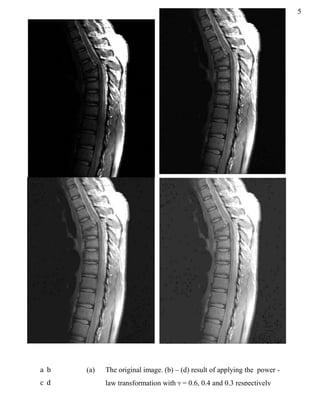

a b

c d

(a) The original image. (b) – (d) result of applying the power -

law transformation with  = 3, 4 and 5 respectively